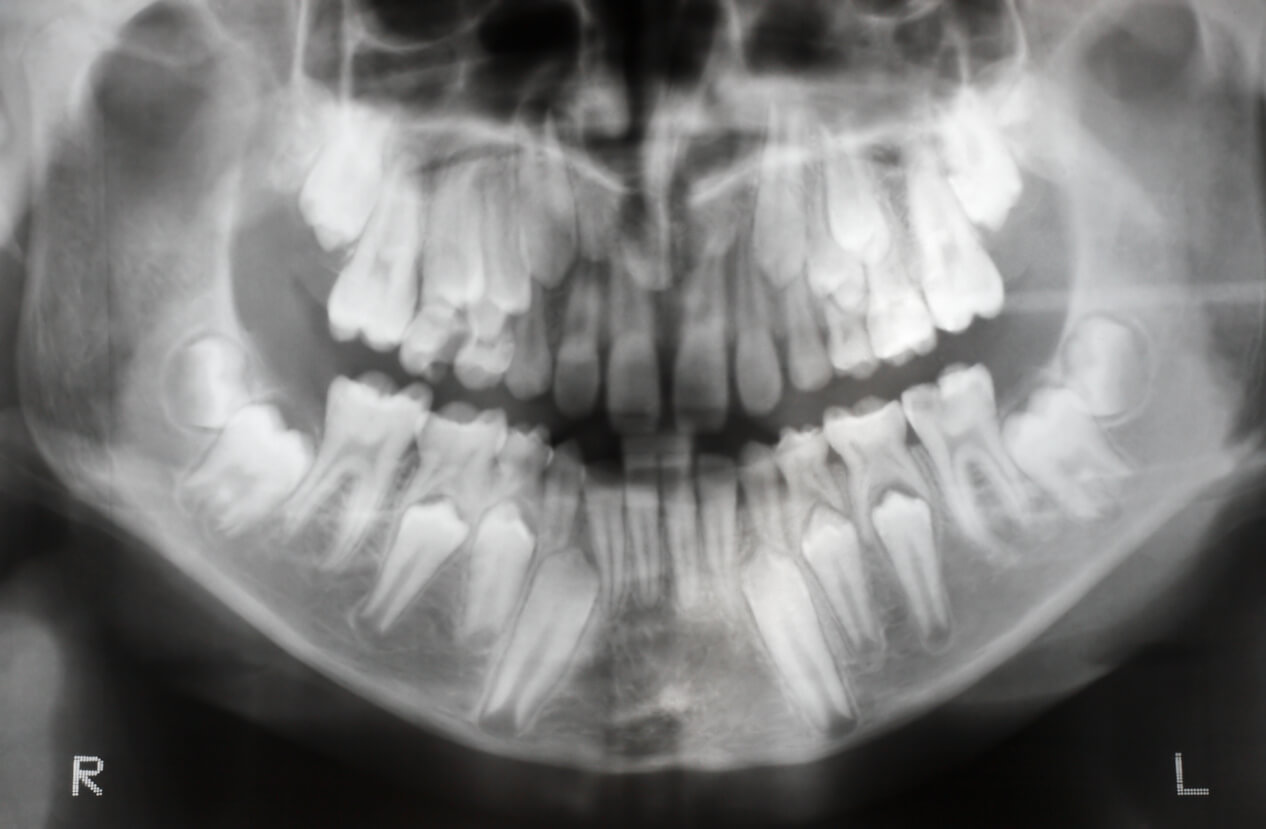

- Orthopantomographie ou « radiographie panoramique » : permet d’observer l’ensemble de la bouche en un seul cliché. Avec une exposition minimale et une procédure simple et confortable, elle fournit une grande quantité de données utiles.